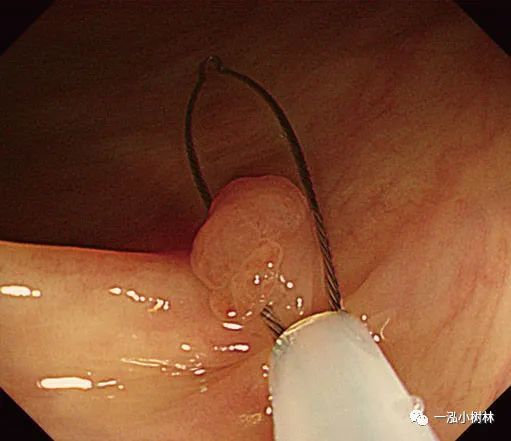

例5 小息肉冷圈套切除术

图5a 横结肠处4mm大小0-IIa型腺瘤

图5b 在病灶上方圈套

图5c 圈套包括病灶周围1-2mm正常黏膜

图5d 对病变进行机械性横切